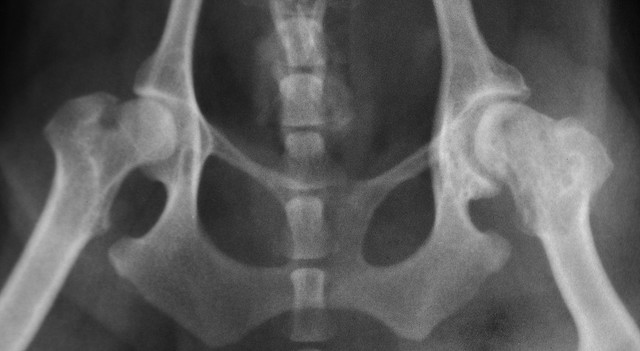

Displazija kolkov je dedno pogojena bolezen sklepov, ki se pojavlja predvsem pri psih večjih pasem. Zaradi nepravilno raščenih kosti kolkov ali zaradi ohlapnih vezi pri psih z displazijo glavica stegnenice uhaja iz sklepov in sčasoma povzroča še druge težave, kot je odpadanje hrustanca in izrastke kosti.

Displazija lahko privede do atropije stegenske mišice. Foto: L. Mahin Wikimedia Commons